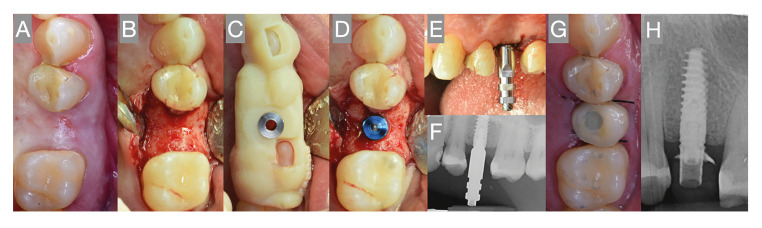

Material and methods: Patients requiring partial rehabilitation with implants in the maxilla were included in a prospective cohort study. In all cases, implant-based restoration with an immediate loading protocol was indicated. A provisional restoration was placed within 72 hours after implant placement. Patient QoL was measured at the first appointment and just before placing the final restoration, using two validated questionnaires. All mechanical and biological complications occurring up until placement of the final restoration were documented. A descriptive and bivariate analysis of the data was performed.

Results: Thirty-five patients with 40 prostheses supported by 60 implants were analyzed. Three implant failures were observed, yielding a 95% survival rate. Five provisional prosthesis fractures and two prosthetic screw loosenings were recorded in four patients. A significant reduction in OHIP-14 score was observed. Likewise, significant differences were found in the results of the QoLFAST-10, with a mean difference in score of 7.3 between the initial and final evaluation.